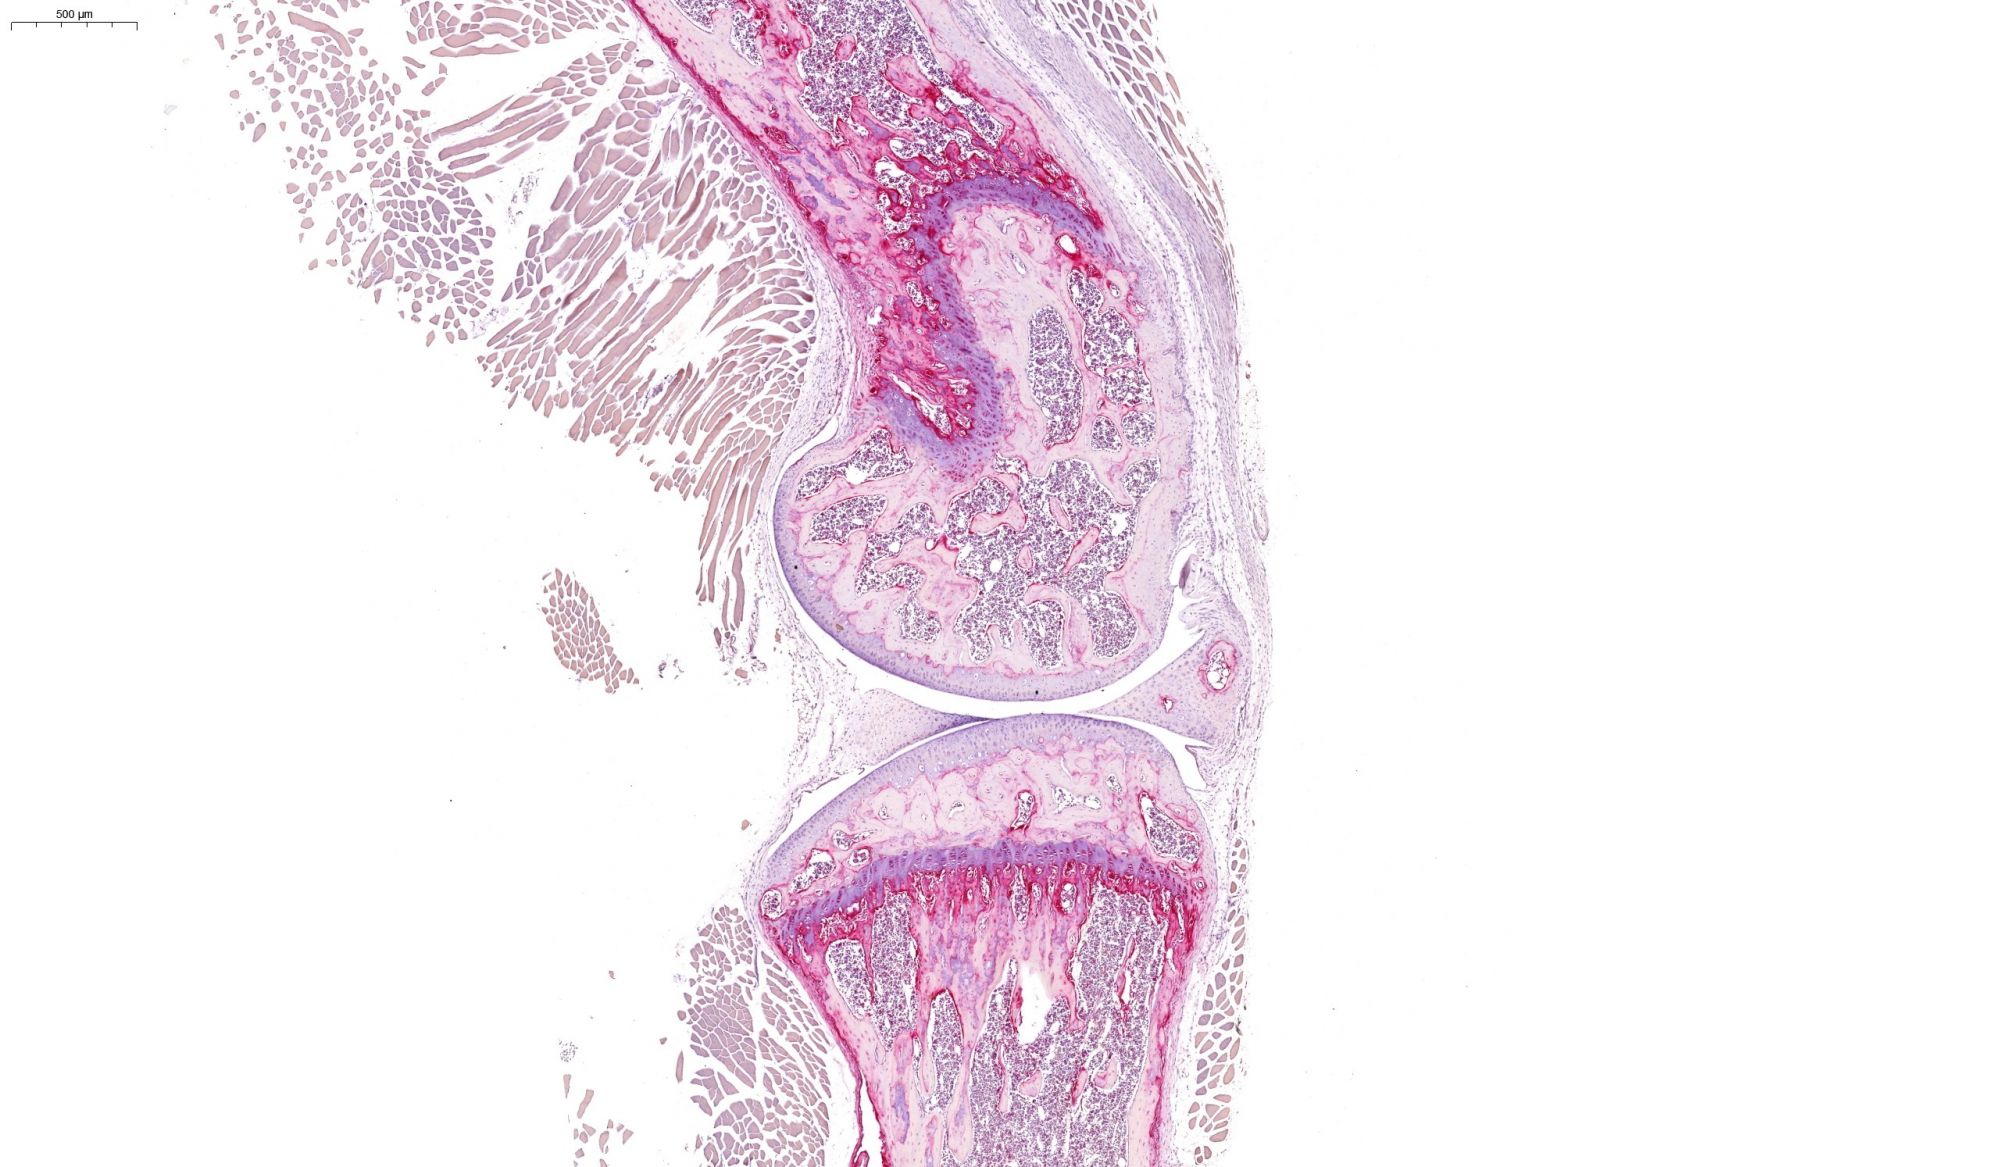

耳組織甲苯胺藍染色

甲苯胺藍染色

247